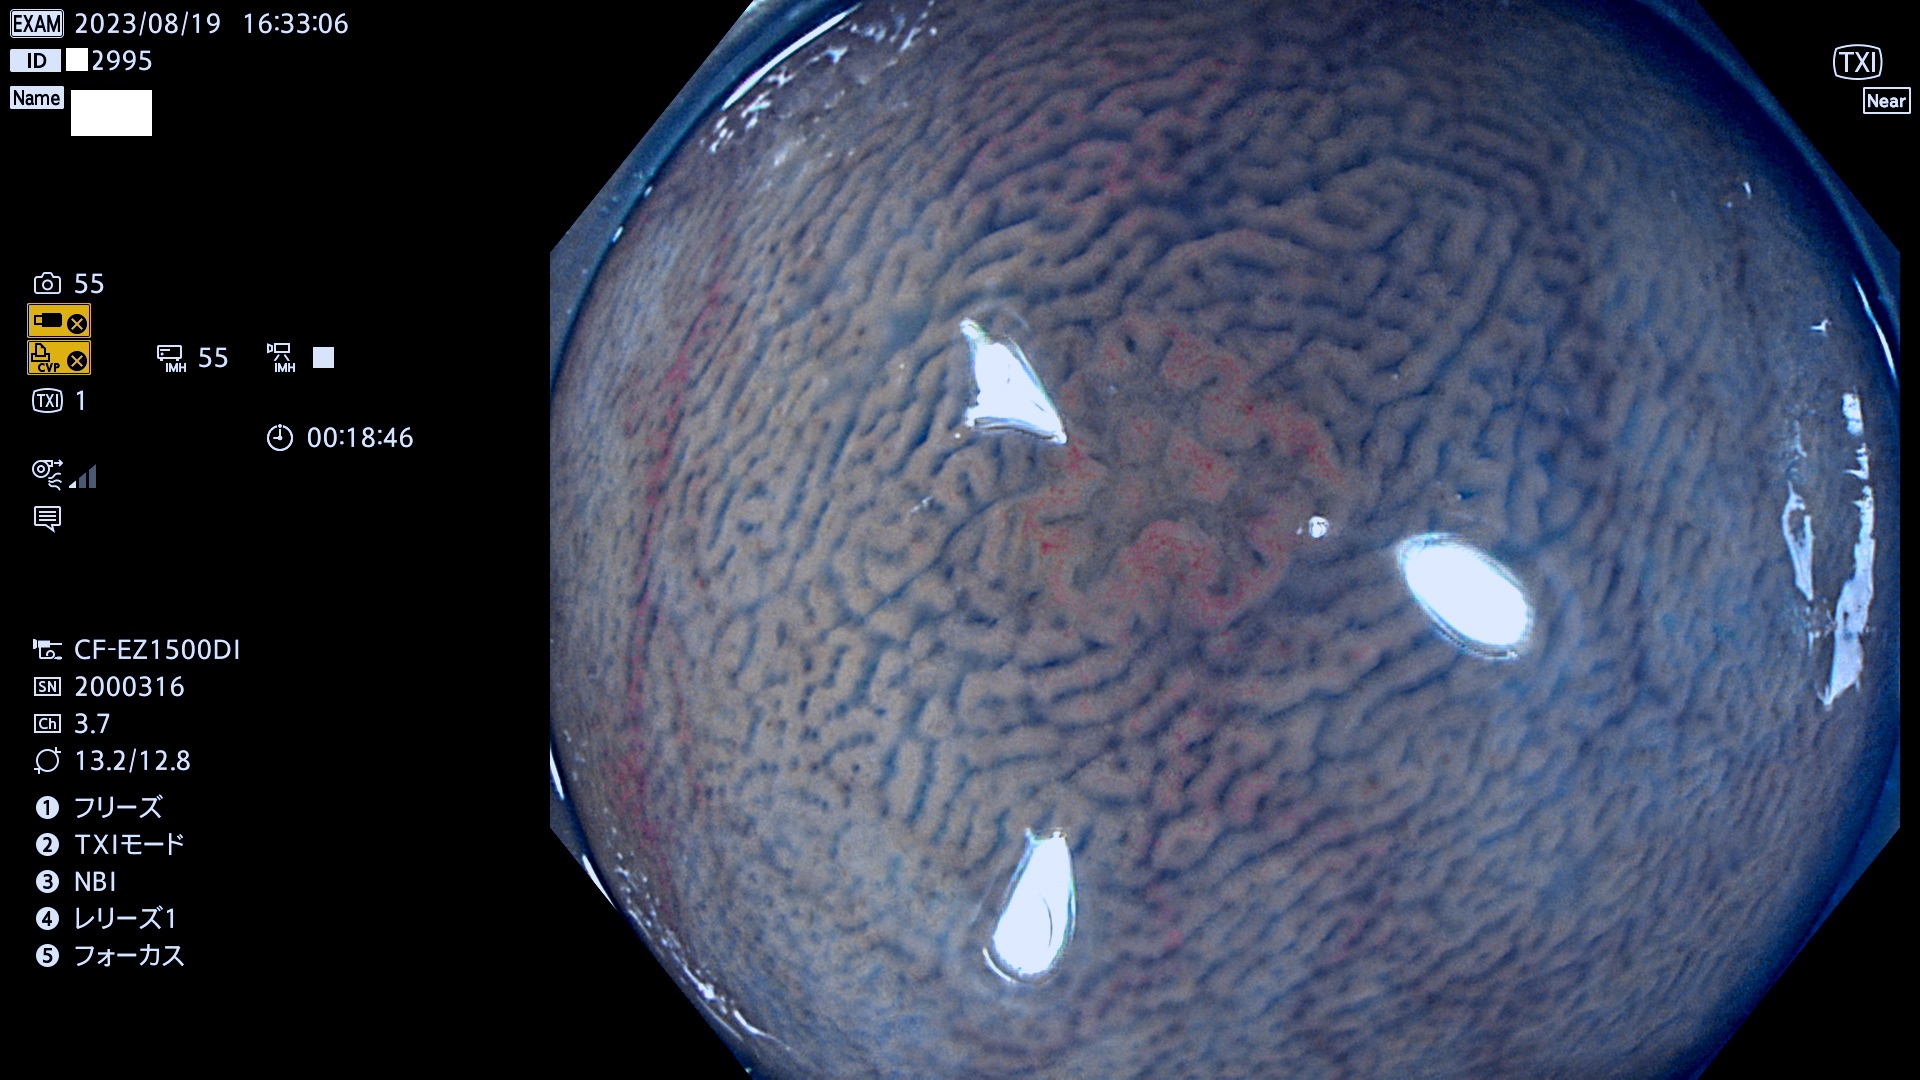

表面型腺腫(Flat Adenoma)の中で、完全に平坦な物をUb、陥凹している物をUcと呼びます。平坦隆起型(Ua)よりも、発見が難しく危険な病変です。このタイプは「内視鏡後・大腸癌の重要犯人」であり、この発見率は「腺腫発見率」よりも、重要な意味があります。

専門的)何故、陥凹していると危険? 癌遺伝子の変異が蓄積すると細胞分裂が盛んになり隆起するのでは?と通常は思われるでしょう。しかし実際は逆です。これは2022年の記事にある「細胞はストレスに直面したら細胞分裂を止める(細胞老化に入り休眠する)という生命の基本的現象」によるものです(Oncogene Stress)。細胞老化を起こすのが癌抑制遺伝子で、この安全装置(ブレーキ)が壊れると癌になります(休眠からの覚醒)。ですから陥凹は「まだ癌では無いが癌化の直前」を意味します。特に「小サイズなのに陥凹している」病変は短期間に腫瘍進化(⇒2021年記事)が起きたことを意味します(=ゲノム不安定性

毎週の検査(木・金・土・日)に発見されたUb、Uc型・腺腫を、その週の日曜の夜にUPし1週間、提示します。

抽出の対象期間 2023年8月17日(木)〜8月20(日)の4日間(48件の検査)11件